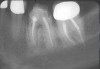

Figure 17  In another case, the mandibular left second molar was fractured and hopeless.

Figure 17

Figure 18  Following hemisection and extraction of the hopeless molar, implants were placed in the first and second molar positions, utilizing specific interradicular bone preparation techniques. Note the positioning of the implant in the second molar site so as to provide adequate dimension for ideal placement of an implant in the first molar area.

Figure 18

Figure 19  A radiograph taken after 46 months in function demonstrates the stability of the crestal peri-implant bone around both implants.

Figure 19